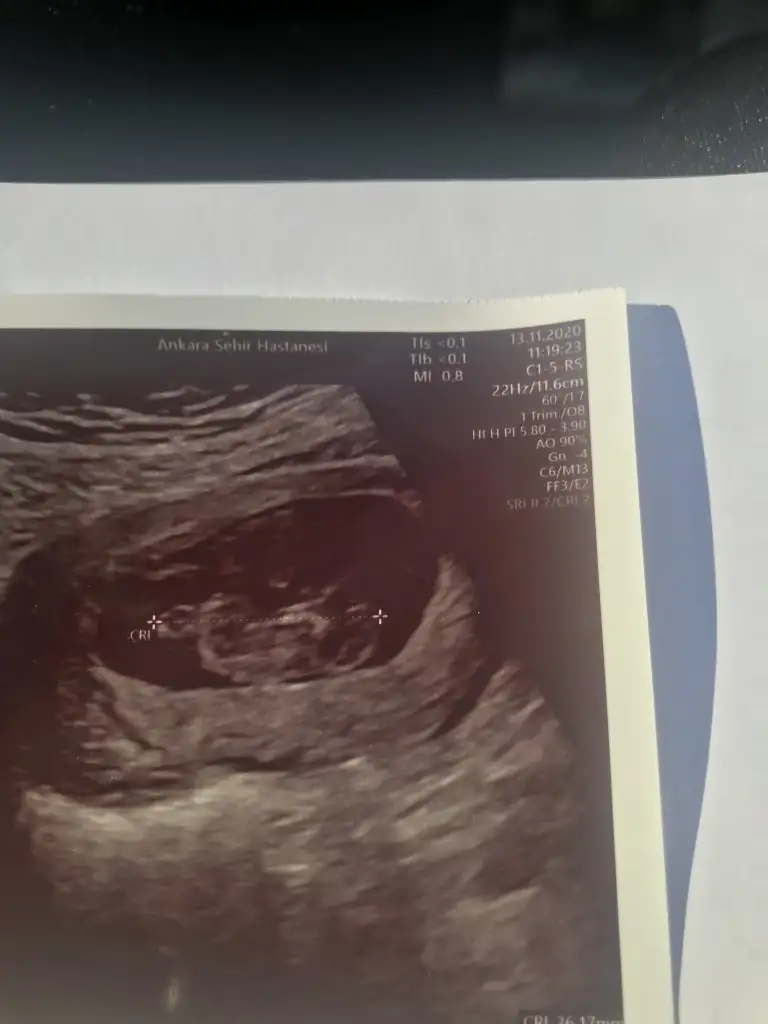

çok tesekkürler maalesef tek bu görüntü varSanki erkek gibi başka USG varsa paylaşın 11 12 13 haftalar olmalı

Bu 11 haftalık:)Orası çok minik nasıl tahmin ederim ki 11 12 13 haftalar olursa paylaşın

Erkek gibi sanki başka USG varsa paylaşınBide ben tahmin alabilirmiyim 12+3 gunluk burda

Erkek gibiIkra meyra tahmin yapabilir misin canım?

Net değil usg11 haftalik ikra meyra hanim tahmin alabilirmiyiz